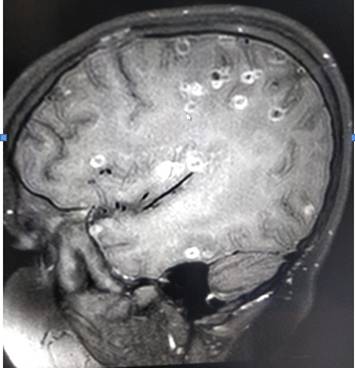

Chụp cắt lớp cho thấy những chấm tròn trong não của bé gái 8 tuổi chính là trứng của sán dây

Praveen Gupta - Giám đốc thần kinh tại Bệnh viện Fortis, cho biết việc chụp cắt lớp phần não của cô bé đã cho thấy hơn 100 chấm trắng hình thành do trứng của sán dây. Việc cơ thể bị xuất hiện các triệu chứng sưng tấy và nhiễm trùng chính là do ăn phải thực phẩm có chứa trứng sán. Khi trứng xâm nhập não bộ qua hệ thần kinh, chúng gây ra chứng loạn thần kinh, biểu hiện thông qua những cơn đau đầu dữ dội, những cơn co giật và tâm lý bất ổn. Có thể nhiều người không biết, nhưng hiện tượng trứng sán dây phá hoại chức năng não bộ là rất phổ biến”.